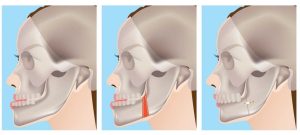

در برخی افراد، یکی از فکها به طور غیرطبیعی بزرگتر یا کوچکتر است. این موضوع ممکن است باعث تراز نامناسب دندانها و مشکلات در بیت (تماس دندانها) شود. در این موارد، جراحی ارتوسرجری برای تعمیق یا کوتاه کردن فک بزرگتر و تصحیح تراز فکی استفاده میشود.

در برخی افراد، فک بالا یا پایین بیش از حد عمودی است. این مشکل میتواند منجر به تراز نامناسب دندانها، مشکلات خوابیدن و تنفس و اختلالات خوردن شود. در این موارد، جراحی ارتوسرجری برای تغییر موقعیت فکها و تصحیح تراز عمودی استفاده میشود.

در برخی افراد، تماس بین دندانهای بالا و پایین نامناسب است که میتواند باعث مشکلات خوردن، گفتاری و درد فک شود. در این موارد، جراحی ارتوسرجری با همکاری ارتودنتیست برای تعمیق یا کوتاه کردن فکها و بهبود تراز بیت استفاده میشود.

در برخی افراد، تراز بین چانه و سایر ساختارهای صورتی نامناسب است که میتواند ظاهر غیرطبیعی و ناهماهنگی صورت را ایجاد کند. در این موارد، جراحی ارتوسرجری برای تصحیح تراز چانه و ساختارهای صورتی استفاده میشود.